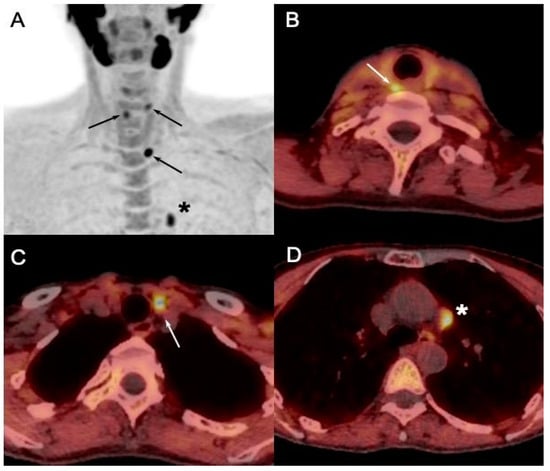

Figure 9. Initial staging in MEN1 patient with primary hyperparathyroidism (PTH: 157 ng/L; calcemia: 2.78 mmol/L) and probable left inferior parathyroid adenoma at cervical US. [18F]FCH PET/CT ((A): anterior MIP; (BD): axial fusion images) confirmed US findings and detected two additional pathological parathyroids (arrows, superior right and left). In addition, hypermetabolic soft tissue nodule (*) of about 10mm was detected in left mediastinum, which suggested pathologic ectopic parathyroid, but turned out to be thymoma (B2) after surgery.

False positive findings can occur during total-body [18F]FCH PET/CT scans, especially in regions of parathyroid ectopy, where the majority may be thymic tumors (Figure 9). Although these findings may be deemed false positives in imaging, they remain noteworthy because diagnosing such tumors in patients with MEN1 carries a poor prognosis and may alter the intended surgical approach [48,49].